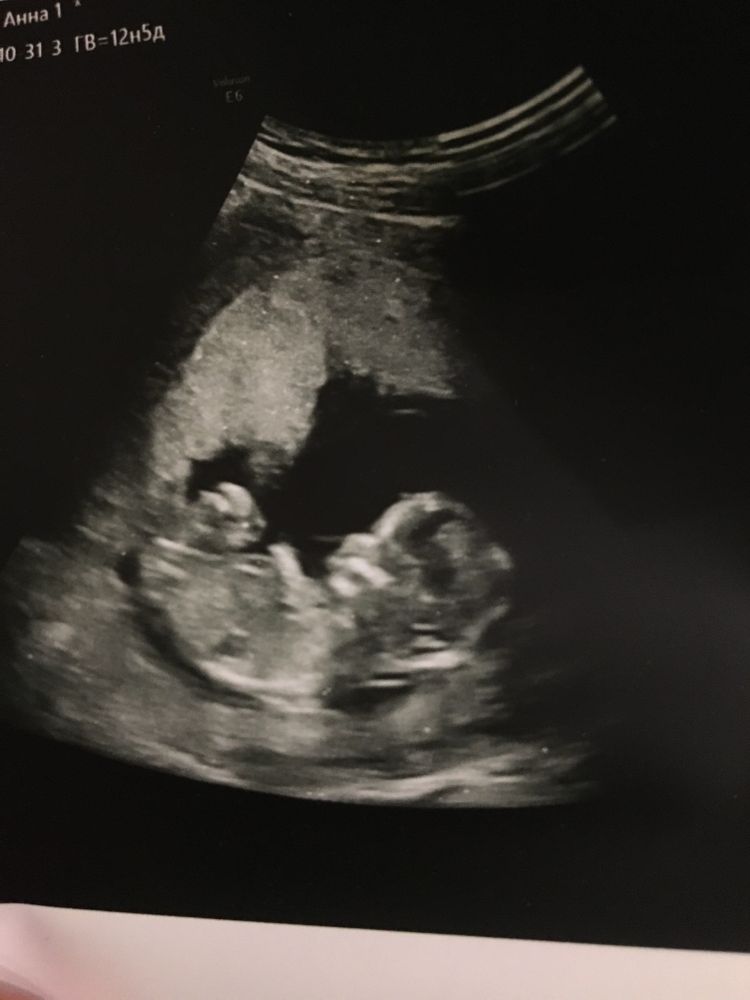

1 скрининг, видно ли пол?

На девочку похоже🙂

Рано) и не видно

Karmilla, она сказала на этом сроке можно увидеть, но ей было трудно развернуть🤷🏻‍♀️

Anya, увидеть можно, но вероятность ошибки велика.Там еще нет половых органов, есть только половой бугорок, он выглядит как писюн, но он и у девочек такой. Из него потом вырастет клитор или писюн, соответственно) поэтому лучше подождите хотябы 16-17 недель, там уже сформировано все) Если конечно ваш инкогнито малыш, или малышка, захочет показать себя 😁😇

На этих фото не видно

Anya, У меня пацанам пол на первом скрининге уже говорили, но у вас на фото ракурс не тот, чтоб пол гадать.... А вообще самое раннее недель в 16 чтоб уж точно.... Ну если узист не криворукий.....

Мальчик?) будить не девайте в следущий раз- не беспокоите его, а заботьтесь ❤️

Рановато

12 недель пол ребенка кого видно 🥰 как часто ошибаются? Это же уже точно девочка?)